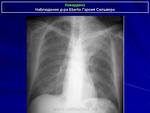

Двусторонняя интерстициальная. Гипертрофия правого корня, перисциссурит малой щели справа. Как бы не вылез центральный справа с лимфогенными метастазами.

В пользу лимфангита еще преимущественное распространение в средних и нижних отделах, неструктурные корни, еще cuffing (разбухание?) стенки бронхов, подчеркнутость междолевых щелей (на боковом хорошо видно, средняя доля "выделена")

Вот и контроль после лечения подоспел...

Динамики нет... К онкологам пойдет?

А клиника после лечения как? Визуально-то - не "айс". Мягко говоря - без динамики.

К онкологам.

Жалоб нет, температуры нет, только кашель с мокротой. Мокрота со слов пациента и жены его светлая, без примесей.